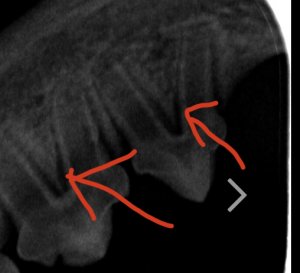

Ich hab zwar hier schon einige röntgenzahnbilder gesehen wo von Knochenabbau die rede war, deswegen hatte ich die Stellen markiert wo es (für mich ) auch so aussah, aber wahrscheinlich ist das in Ordnung so. Ich hoffe ja dass sich dazu noch jemand meldet und mir grünes Licht gibt.

Ansonsten werd ich einfach nochmal beim Arzt nachfragen ob das wirklich in Ordnung ist.